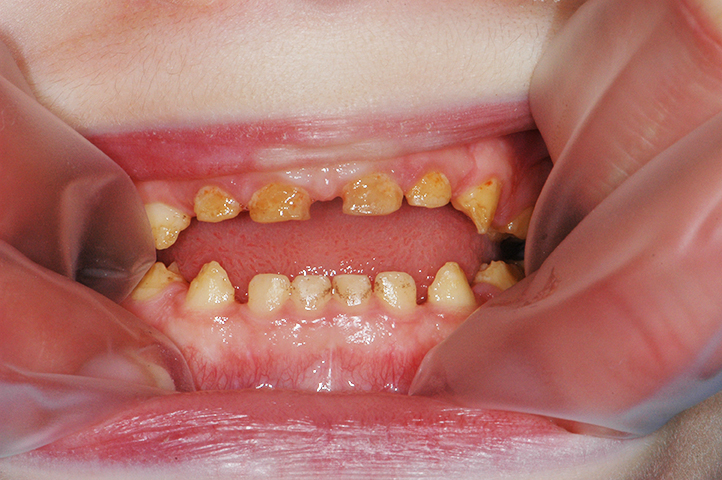

3) Une atteinte de toutes les dents et des deux dentures est le signe d’une étiologie génétique. Il s’agit des amélogenèses imparfaites (AI).

Les amélogenèses imparfaites représentent un groupe hétérogène d’altérations de l’émail d’origine génétique. Leur prévalence varie de 1/700 à 1/14000 selon les études et tous les modes de transmission ont été décrits, autosomique dominant, récessif, lié à l’X ; des cas sporadiques ont également été rapportés. Le processus de formation de l’émail est altéré et conduit à la modification de la structure et de l’apparence clinique de l’émail.

Selon le type de défaut principal, l’AI peut être qualifiée d’hypoplasique, d’hypominéralisée ou d’hypomature. Plusieurs formes peuvent coexister dans une même famille, chez un même patient, voire sur une même dent, ce qui complique le diagnostic. L’expression des nombreux gènes, et l’implication de différentes protéines expliquent ces formes d’AI si différentes (Tableau I).

Les conséquences cliniques des AI sont multiples et potentiellement sévères :

• dyschromie : c’est l’anomalie de teinte des dents, par exemple des taches blanchâtres, un aspect jaunâtre, voire brunâtre des dents

• hypersensibilité (douleurs au froid, au brossage, à la mastication par exemple)

• pertes de substance.

Dans la plupart des formes d’AI, l’aspect esthétique est fortement compromis. En effet, l’émail étant très fin, voire absent, la couleur de la dentine devient apparente, conférant à la dent une teinte jaunâtre voire brunâtre. Enfin, l’usure prématurée de l’émail et les pertes de substance associées à une rétention accrue de plaque sont susceptibles d’augmenter le risque carieux.